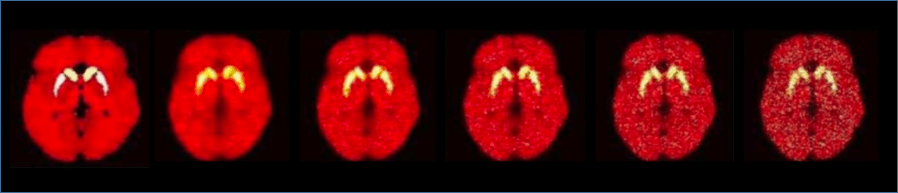

A C++ & Matlab-based PET simulation and reconstruction software, enabling realistic brain simulations, e.g. dynamic PiB PET imaging, based on the system matrix of the advanced brain-dedicated High Resolution Research Tomograph (HRRT) scanner.

- Can simulate dynamic PET studies, with an initial table of kinetic K values; e.g. our default example performs dynamic PiB PET studies